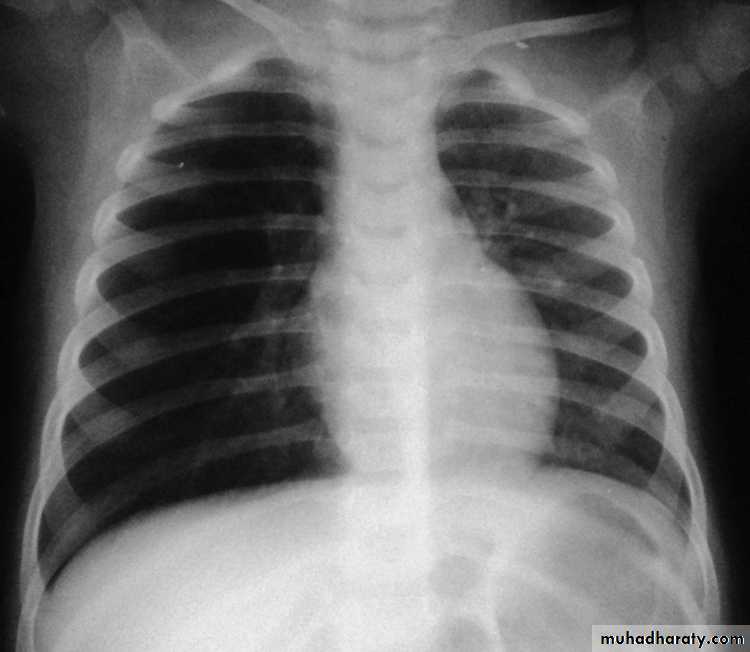

Radiopaque hemi-thoraxPneumothorax (air in pleural space )

Signs

Loss of vascular markings at the outer parts of lung fieldsDemarcating pleural line between the lung & vessels lacking area.

Well demarcating of the scapula

Epsilateral lung collapse

Tension pneumothorax

Emergency condition

Pressure effect on the mediastinum & major vessels

Treatment by chest tubes